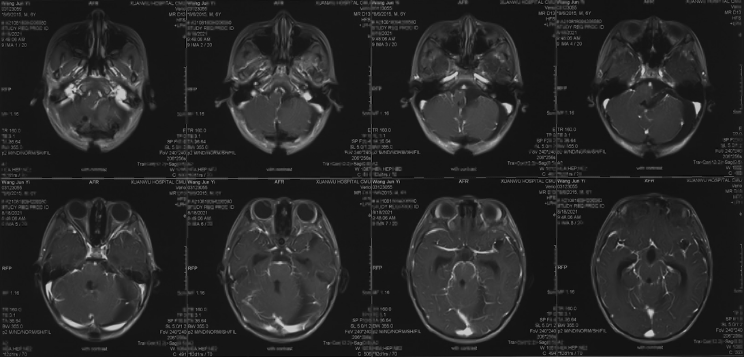

Pre-operative imaging

Preoperative imaging MRI-T2

Preoperative imaging MRI-T1

Preoperative MRI-DWI

Preoperative CT